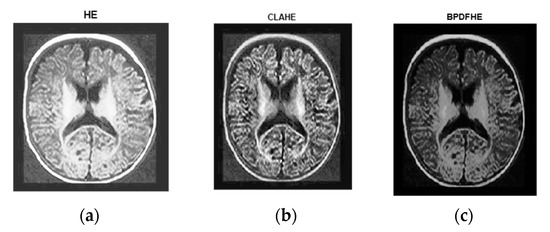

The following figures are the enhanced images with their corresponding histograms (HE, CLAHE, and BPDFHE) for the original images.

Figure 4a is the original. Figure 4b is its histogram representation. Figure 5a–c represents the same image enhanced via different preprocessing methods, i.e., HE, CLAHE, and BPDFHE, and Figure 6a–c is their respective histograms.

Preprocessed with (a) HE, (b) CLAHE, and (c) BPDFHE.

Figure 7a is the original image. Figure 7b is its histogram representation. Figure 8a–c represents the same image enhanced via different preprocessing methods, i.e., HE, CLAHE, BPDFHE, and Figure 9a–c is their respective histograms.